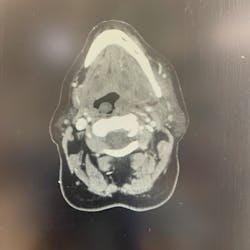

Signs of a facial infection include facial asymmetry in the form of swelling on one side of the face. The face will feel firm, warm, and tender to the touch, and redness of the skin will develop in time. It often starts with dental pain or tooth pain inside the mouth. It can also be pain inside the mouth around the tooth. As it progresses, you may see some intraoral drainage coming from the associated tooth. Infections originating from the skin will often present with external drainage. Severe odontogenic (caused by a bad tooth) infections may even spread and become so large they break through the skin.

There are some spaces around the face, called potential spaces, where the fluid can collect. Some of the spaces inside the jaw and adjacent to the throat can get very dangerous. That’s why it’s important to treat facial abscesses as soon as possible, usually within 24 hours.

The most important concern with any significant facial infection is always going to be the airway. Serious and worrisome signs are when patients have difficulty breathing, difficulty swallowing or pain with swallowing, trouble breathing if they lie flat, or if they have to sit up to breathe. In these situations, the abscess is impinging on the airway.

Significant facial infections that require surgery are taken care of in a hospital setting. The patient is admitted to the hospital, started on IV antibiotics and pain meds, and planned for surgical incision and drainage (commonly called I&D) often within 24 hours, based on the severity and immediate risk of spread. Patients can expect a one- to three-day hospital stay depending on their response, recovery, and need for monitoring. During the hospital stay, the patient remains on antibiotics and pain meds through an IV, both of which will be converted to oral medications upon discharge. Most surgeons also require at least one postoperative visit to check progress.